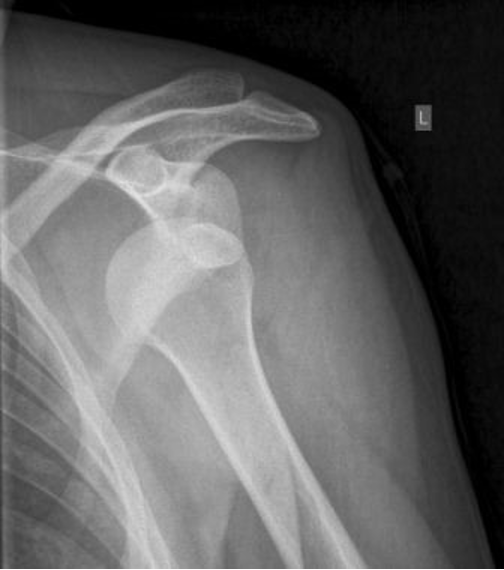

Bij dit letsel zit de kop (= onderdeel is van het bovenarmsbot), niet meer in zijn kom (= onderdeel van het schouderblad), waarbij het kapsel van de schouder overrekt is geraakt. Dit ontstaat meestal door een val op de arm of hand, waarbij tevens de schouder naar buiten is gedraaid. De kop schiet er meestal aan de voorkant uit, maar dat kan ook naar achteren of naar onderen gebeuren.

Vaak wordt er bij het lichamelijk onderzoek al een afwijkende stand van de schouder gezien. Op de aanvullende Röntgenfoto is meestal wel goed te zien dat de schouder uit de kom is. Soms gaat het uit de kom zijn gepaard met een breukje van de schouderkop of kom.